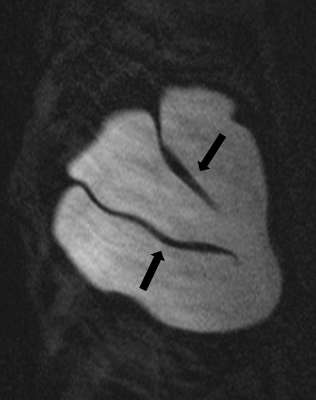

Fully collapsed intracapsular ruptures appear as multiple hypointense curvilinear lines that float within the hyperintense silicone gel, referred to as the “linguine sign” (Figure 4). The floating curvilinear lines represent the collapsed outer shell6.